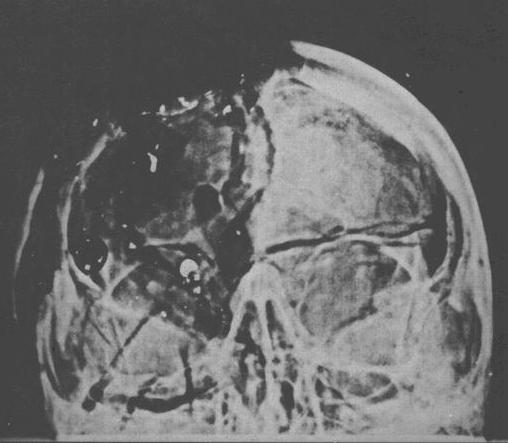

HSCA Appendix Volume 7

Figure 20, Page 112

Oswald Theorists claim that there is damage to the top-front

of the skull where the alleged rear bullet exited, but

claim that no bullet entered or exited the temple. Contrarily,

compare the left intact temple to the right damaged

temple

in HSCA Figure 19. Also notice the missing

temple bone in HSCA Figure 20. (click X-Rays to enlarge)